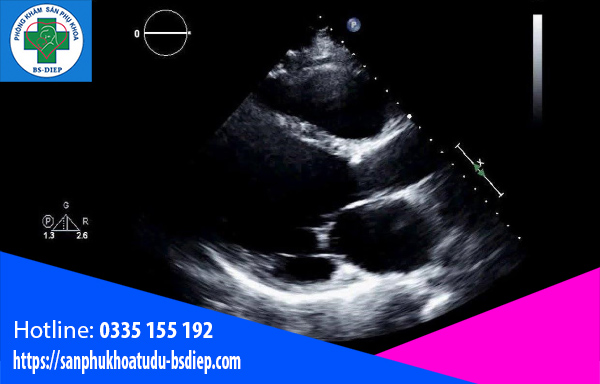

Phương pháp siêu âm

Đôi khi, thai 7 tuần chưa có tim thai là do phương pháp siêu âm khám thai định kỳ. Trong một vài tình huống, siêu âm có thể không mang lại kết quả rõ nét và nhận biết tim thai. Đặc biệt, đối với những thai phụ có cơ thể hơi mập thì rất khó trong việc tìm và nghe thấy hoạt động của tim thai.

Chính vì thế, để xác định rõ tim thai, bác sĩ có thể yêu cầu thai phụ thực hiện một số xét nghiệm khác như xét nghiệm beta HCG.